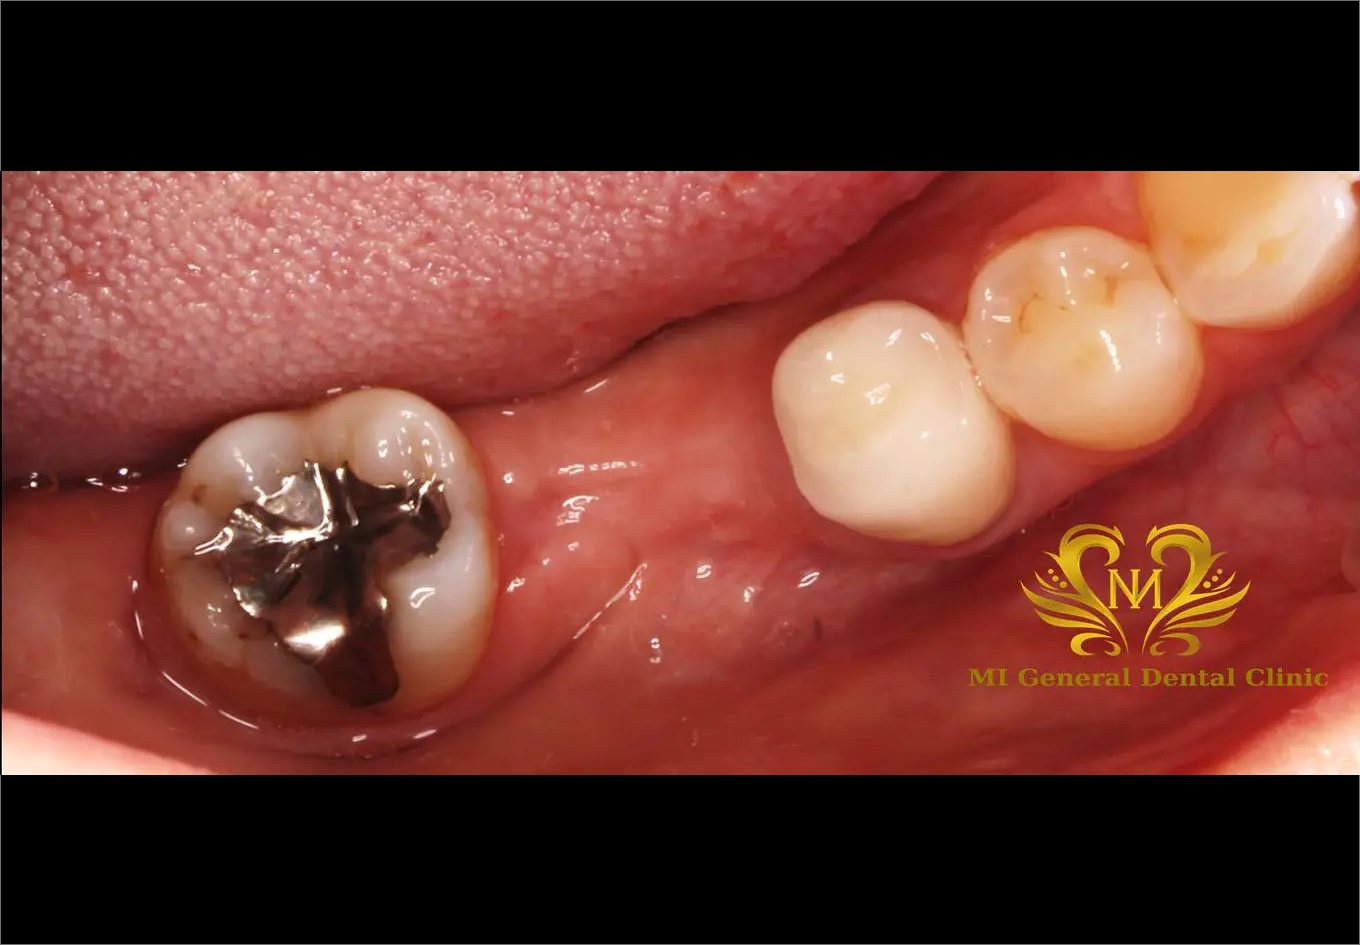

治療前

右下の奥歯の歯がありません。

右下の奥歯が1本ありません。

歯を抜歯して噛みにくい。